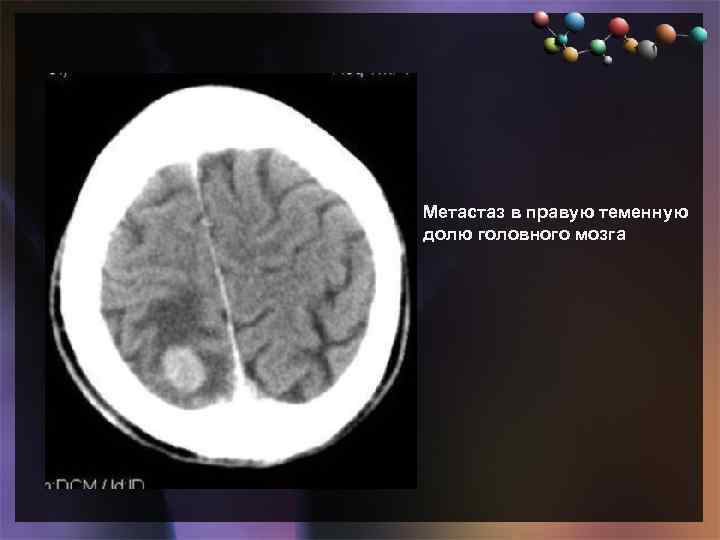

• Подзаголовок слайда Метастаз в правую теменную долю головного мозга

• Подзаголовок слайда Метастаз в правую теменную долю головного мозга